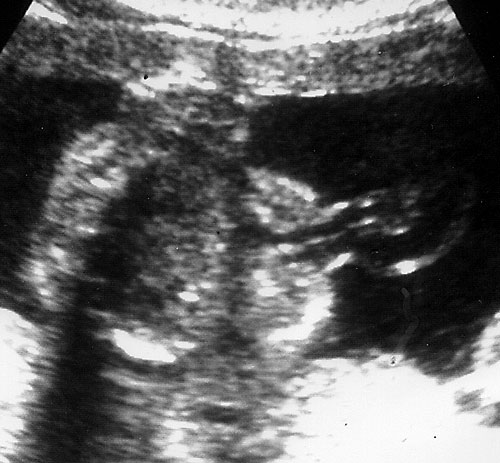

Normal nose and lips seen in coronal "swimmers view". - Sagittal view of face to visualize profile.

Normal sagittal view of fetal face.